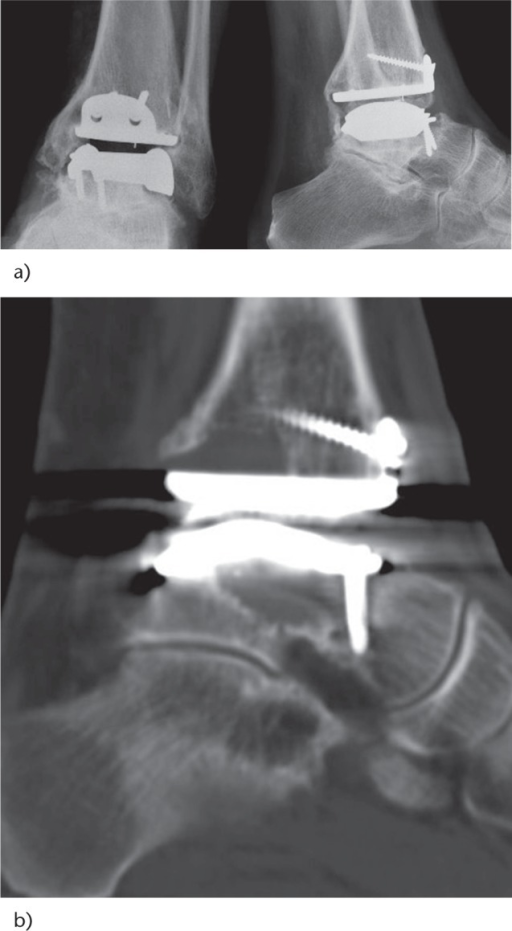

Clinical image for Total Ankle Arthroplasty

Source: Total Ankle Arthroplasty Radiograph • PMC5367591 • CC-BY

Describe the key principles and surgical technique for total ankle arthroplasty.

What are the common complications of TAA? How would you manage early failure?